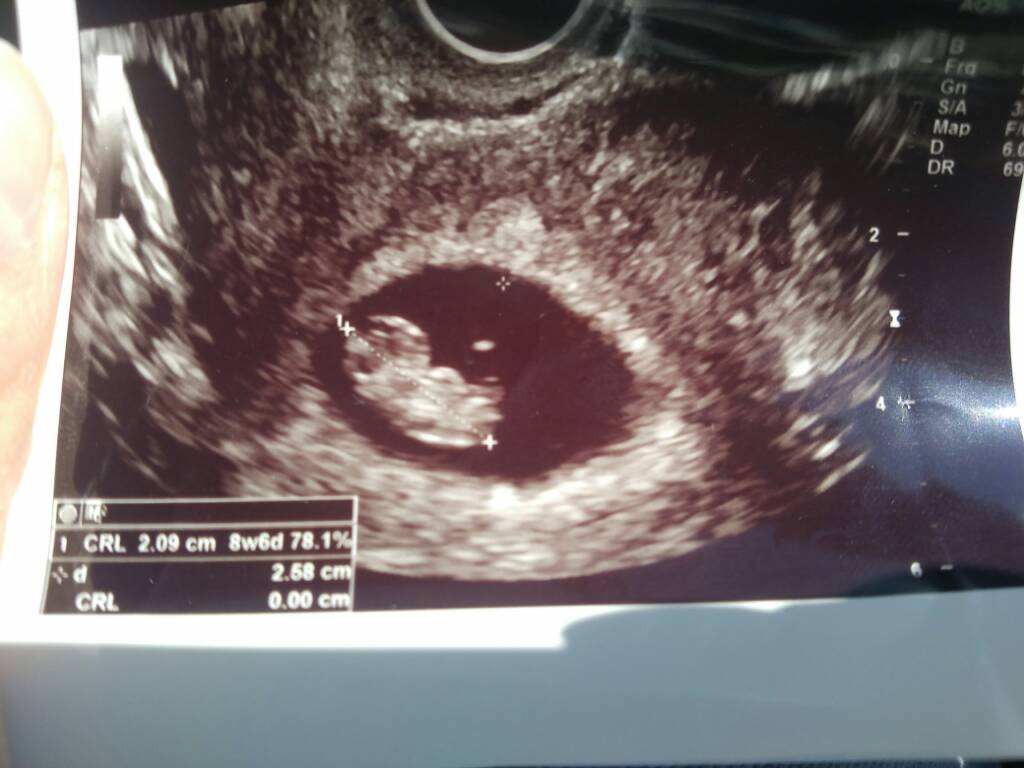

Okruszek pięknie rośnie, serduszko bije 161 uderzeń na minutę. Krwiaka nie ma. Wszystko jest ok. Dziś według USG 9t0d, według miesiączki 8t1d. Maleństwo ma 2.32cm. Termin porodu 15/16.02 [emoji6]. A tu przedstawiam wam mojego okruszka [emoji2]Zobacz załącznik 877136

Moje drogie Panie, oto Dzidziul w całej okazałości [emoji7] 4 dni starszy niż z terminu OM. Krwiaka nie ma!!!!! Tak, poryczałam się. Jak to lekarz powiedział "serduszko aż bije po oczach" z emocji nie zapytałam ile uderzeń, ale pewnie 167 [emoji14] dziękuję za wszystkie kciuki i dobre słowa [emoji173]

Moje drogie Panie, oto Dzidziul w całej okazałości [emoji7] 4 dni starszy niż z terminu OM. Krwiaka nie ma!!!!! Tak, poryczałam się. Jak to lekarz powiedział "serduszko aż bije po oczach" z emocji nie zapytałam ile uderzeń, ale równie 167 [emoji14] dziękuję za wszystkie kciuki i dobre słowa [emoji173]Zobacz załącznik 877188